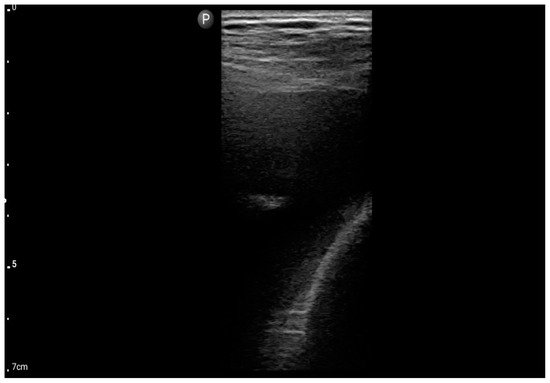

Figure 5.

Convex probe; view: lungs, two intercostal spaces-“Merlin space” with B-profile (BLUE protocol), (source: author’s material—DK).

Figure 6.

Linear probe; view: Costodiaphragmatic recess—pleural effusion (BLUE protocol) (source: author’s material—DK).